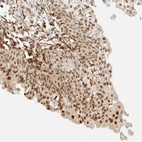

Immunohistochemical staining of human urinary bladder shows strong nuclear positivity in urothelial cells.